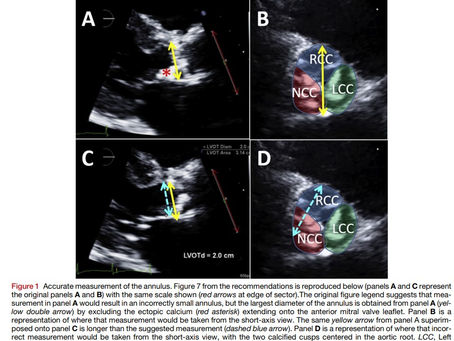

MEDICIÓN PRECISA DEL DIÁMETRO DEL TRACTO DE SALIDA DEL VENTRICULO IZQUIERDO

Accurate Measurement of Left Ventricular Outflow Tract Diameter: Comment on the Updated Recommendations for the Echocardiographic...